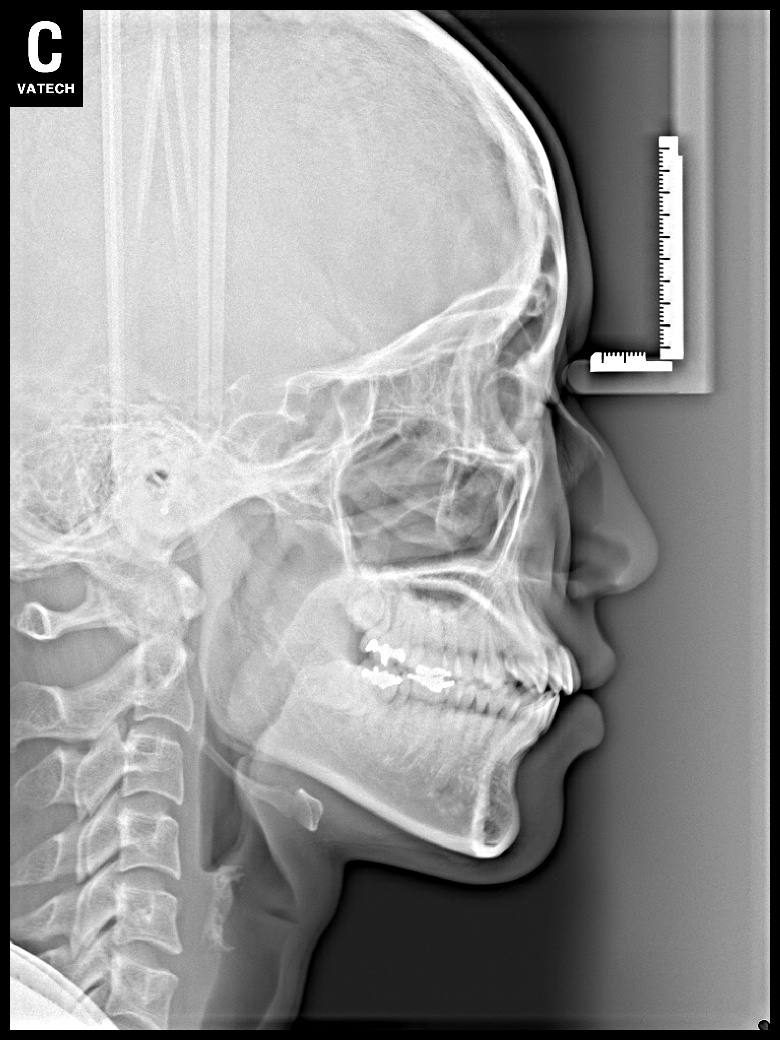

치료 전 사진입니다.